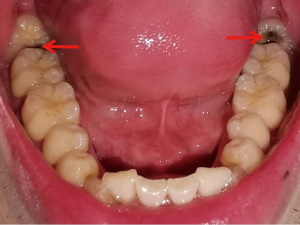

The frontal occlusal photo required the patient to expose the maximum number of teeth and gums and could be assisted by common objects. The upper teeth photo required the patient to open the mouth as much as possible and take a picture of the maxillary dentition. The patient was required to lie as flat as possible, with the maxillary occlusal surface at 90–120° to the floor after opening the mouth. The handpiece was held as low as possible, depressed or held upside down, and the full maxillary arch was photographed from the bottom up. The patient’s head was lowered slightly and their thumb and index finger were held slightly apart at the corner of the mouth while the handpiece was held diagonally upwards towards the bottom. For patients with smaller mouth openings, one photo of each of the right- and left-side teeth could also be taken. No pre-setting of lighting conditions, resolution, exposure, and other jumps in the photographic process were made for this study; all images were obtained by the device in the conventional photographic mode. In order to approximate the image effect in real-life scenarios, all images were captured using a smartphone and without professional equipment such as reflectors (Figures 1,2).

The images were collected in JPG format, with a size of 1–33 Mb. A total of 640 images were collected, and the image annotation software LabelImg (labelImg.1.8.4. November 2020. Tzu Ta Lin. https://pypi.org/project/labelImg/1.8.4/.10/12/2020) as used to annotate the caries in the image data (Figure 3).